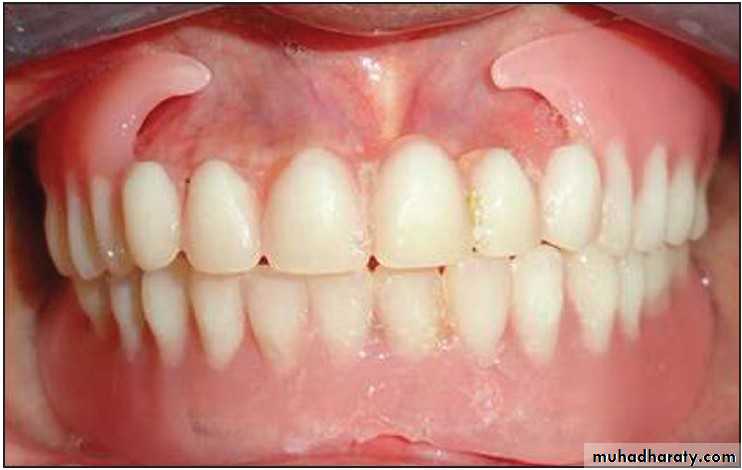

An immediate denture is defined as a denture that is made prior to the extraction of the natural teeth and inserted into the mouth immediately after the extraction of those teeth. It may involve total or partial replacement.3

1 . Maintenance of the soft tissue contour of the face

2. Denture will support the soft tissue around the face in their correct position once teeth are lost.

4 . Esthetic are maintained by placing the artificial teeth in a position similar to natural teeth or improved by changing the position.